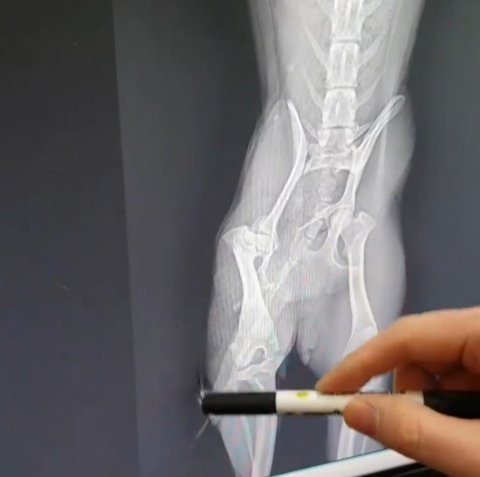

그래서 동물병원에 갔는데 교통사고로 다리가 3곳이나 골절된 상태였던거야

다리가 부러진 채 최소 2년정도 앞도 안보이는 상태로 떠돌이 생활 한거야......

부러진 뼈가 변형이 있어서 잘못 생겨난 뼈를 제거하는 수술을 했어

수술후에도 오른쪽 뒷다리가 땅에 닿지 않아.. 다리뼈가 다 틀어졌나봐ㅠ